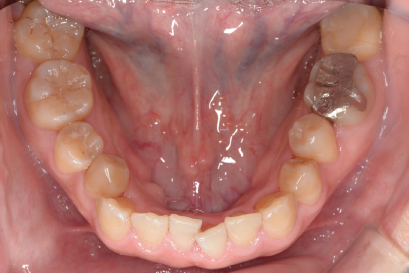

術後

年代、性別

20代、男性

職業

学生

主訴

歯並び相談

部位

抜歯を併用してのインビザラインによる全顎矯正

治療期間

1年6ヶ月

矯正費用

95万円

施術説明

他院の矯正専門医院でマウスピース矯正は不可能と言われて、セカンドオピニオンで来院されました。就職活動が始まるまでに、歯並びを治療しておきたいということでしたが、当院の矯正専門医であるインビザライン・ファカルティーの山本先生による検査では、インビザラインで治療が可能と診断されました。抜歯を伴う矯正は通常長期にわたる事が多いですが、1年半で治療も完了し非常に喜んでもらえました。

副作用・リスク

なし